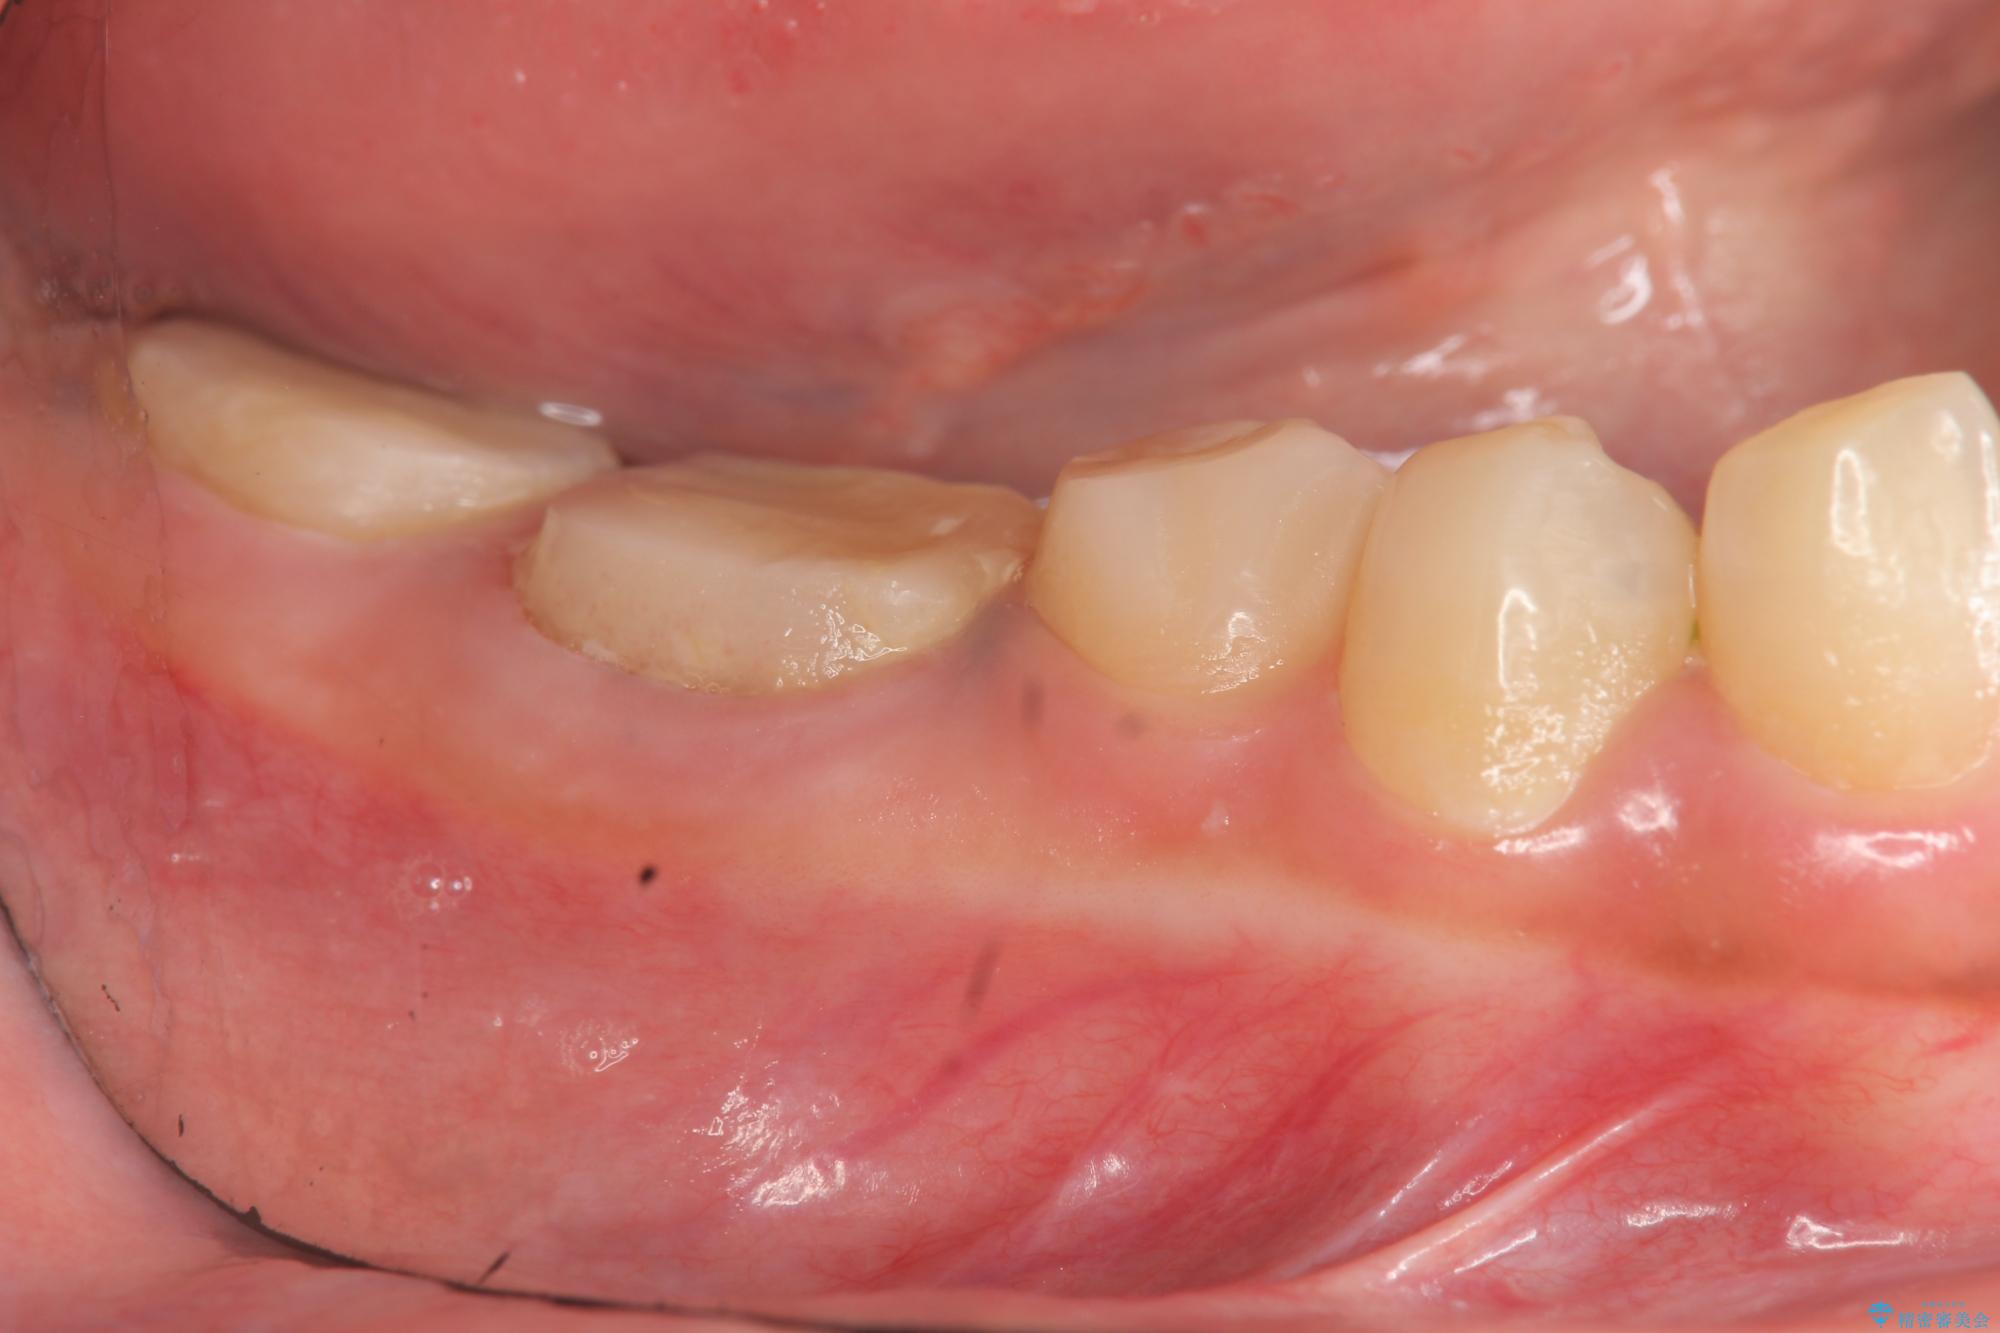

奥歯は既に根管治療が為されクラウンを装着する必要性がある状態ですが、歯の高さが低くクラウンの安定性・強度を担保するために歯周外科を行う治療計画としました。

歯周外科を行うことで、歯ぐきの位置を下げ歯の高さを作り出し安定したクラウンの装着が可能となります。また同時に舌の邪魔となっていた骨隆起の除去を行うこととしました。